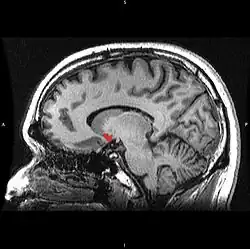

| Прилегающее ядро на МРТ головного мозга человека |

Сенсибилизация — концепция в психологии, объясняющая тот феномен, что люди после повторного приема вызывающего болезненное пристрастие вещества, независимо от вызываемого им чувства удовольствия и часто вопреки пониманию вреда, испытывают ещё большее пристрастие и тягу к повторному потреблению[1][2]. Концепция была предложена на основании опытов, в ходе которых экспериментальным животным вводили психостимуляторы, причём повторное введение лекарства вызывало усиленную психомоторную реакцию на введение прежней дозы[3][4]. Считается, что причина этого явления может быть связана со стойкими изменениями в прилежащем ядре, компоненте так называемого центра удовольствия.

Сенсибилизация — в разной степени выраженный у разных индивидов, специфический в отношении определенного вещества эффект, не связанный с перекрёстными реакциями, хотя она также может быть эффектом многих индуцирующих зависимость лекарств. Этот процесс является противоположностью формированию привыканию (габитуации). Сенсибилизация приводит к снижению чувствительности в области прилежащего ядра. Вследствие этого, ядро может активироваться уже минимальными дозами, а иногда и ассоциированными с наркотиком раздражителями. Так возникает «управляемая влечением» мотивация с импульсивным побуждением к действию. Эта мотивация манифестирует, прежде всего, в таких подкорковых центрах как полосатое тело. Эта так называемая «возбуждающая сенсибилизация» может объяснить феномен, заключающийся в том, что зависимый от какого-либо вещества больной, независимо от субъективного чувства удовольствия, испытывает чувство, вынуждающее снова найти и принять соответствующее наркотическое вещество. При этом данный процесс и следующие за ним действия и поступки в их целенаправленности не воспринимаются больным как насильственные, так как в этом случае не обязательно дело доходит до осознанной непреодолимой потребности в соответствующей субстанции.

Нейробиологический коррелят процессов сенсибилизации не вполне ясен. Возможно, этот процесс вносит решающий вклад в так называемою «наркотическую память», причем в её реализации, как полагают, участвует взаимодействие многих структур (в том числе, гиппокампа). В этой связи можно думать о вовлечении в процесс стойких изменений дофаминергической нервной передачи в прилежащем ядре, например, о повышении активности дофамина или сенсибилизации D1-дофаминовых рецепторов. Считается, что играть решающую роль при этом может развитие долгосрочного потенцирования в вентральном отделе полосатого тела и обусловленное им изменение глутаминергической нервной передачи[3].